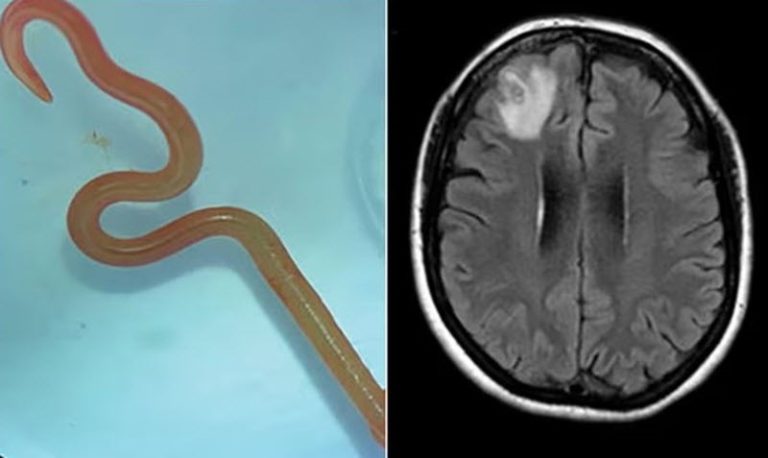

دودة حية بطول 8 سم في دماغ امرأة!